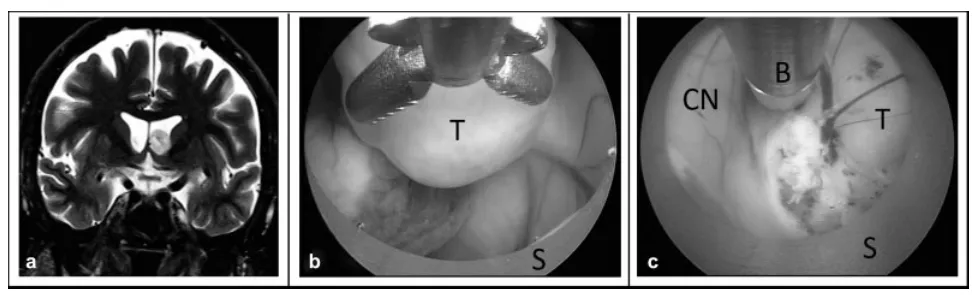

狭窄脑室内的内镜肿瘤切除术。 (a) 冠状位T2加权磁共振图像显示侧脑室内肿瘤,脑室空间狭小。 (b) 将内镜向鞘管内回缩,以创造额外工作空间。 (c) 使用鞘管将肿瘤从尾状核牵开,以便显露肿瘤基底并用双极电凝处理。缩写:B,双极电凝电极;CN,尾状核;S,内镜鞘;T,肿瘤。